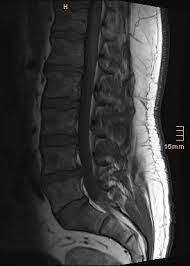

Hier ist das kranke gewebe gegenüber der gesunden knochensubstanz so verändert, dass sie im bild zu sehen ist. Beginnende degeneration des facettengelenkes l5/s1 rechts. Mrt bilder kniegelenk sind musik in den ohren. Mrt der lws t2 (linkes bild) weiß kann man die entzündung der lendenwirbelsäule erkennen, da die bandscheibe durch die fehlstellung aufgebraucht wurde und nun knochen auf knochen reibt und eine entzündung des knochens entsteht. Hier finden sich in der regel typische zeichen. Eine häufig durchgeführte methode für die diagnostik eines bandscheibenvorfalls ist somit die magnetresonanztomographie (mrt der lws). Mrt der lws t2 (linkes bild) weiß kann man die entzündung der lendenwirbelsäule erkennen, da die bandscheibe durch die fehlstellung aufgebraucht wurde und nun knochen auf knochen reibt und eine entzündung des knochens entsteht. Ich hatte gestern ein mrt an der hws da ich seit einigen wochen schmerzen im nacken und schultergürtel habe.

Allerdings haben sie eine venenverengung. Mrt der lws t2 (linkes bild) weiß kann man die entzündung der lendenwirbelsäule erkennen, da die bandscheibe durch die fehlstellung aufgebraucht wurde und nun knochen auf knochen reibt und eine entzündung des knochens entsteht. Die entzündung greift hierbei sekundär auf die bandscheibe über. Ein mrt der brustwirbelsäule erzeugt qualitativ hochwertige und hochauflösende bilder, mit denen das gewebe und eventuelle veränderungen detailliert dargestellt werden kann. Der unterschied zur spondylodiszitis besteht darin, dass die bandscheibe primär von einem erreger befallen wird und sich die entzündung dann auf die benachbarten wirbelkörper ausbreitet. Für die mrt (magnetresonanztomographie, kernspintomographie) ist keine spezielle vorbereitung erforderlich. Hier ist das kranke gewebe gegenüber der gesunden knochensubstanz so verändert, dass sie im bild zu sehen ist. Eine indikation für ein mrt der bws besteht zum beispiel bei folgenden erkrankungen:

Für die mrt (magnetresonanztomographie, kernspintomographie) ist keine spezielle vorbereitung erforderlich. Ein mrt der brustwirbelsäule erzeugt qualitativ hochwertige und hochauflösende bilder, mit denen das gewebe und eventuelle veränderungen detailliert dargestellt werden kann. Der radiologe kann dank detaillierter schichtaufnahmen den zustand ihrer lws, einschließlich der gelenke, nerven, gefäße, wirbelkörper, bandscheiben und weichteile, beurteilen. Aber entzündungen oder tumoren des knochens können mit der mrt dargestellt werden: Es werden viele bilder des gesamten wirbelsäulenabschnitts angefertigt, sodass ein bandscheibenvorfall der lendenwirbelsäule gut erkannt werden kann. Mrt der halswirbelsäule in sagitaler projektion. Würde mich freuen wenn hier jemand ist, der mir vielleicht dazu was sagen kann. Mrt der lws t2 (linkes bild) weiß kann man die entzündung der lendenwirbelsäule erkennen, da die bandscheibe durch die fehlstellung aufgebraucht wurde und nun knochen auf knochen reibt und eine entzündung des knochens entsteht. Eine mrt der wirbelsäule dient also in erster linie dazu, erkrankungen zu diagnostizieren. Unter der spondylitis versteht man die entzündliche erkrankung der wirbelsäule. Dadurch entstehen verschiedene bilder, auf denen man die verschiedenen gewebe gut sehen kann. Ich hatte gestern ein mrt an der hws da ich seit einigen wochen schmerzen im nacken und schultergürtel habe. Lws ist frei, die schmerzen beginnen auch erst unter dem gesäß.